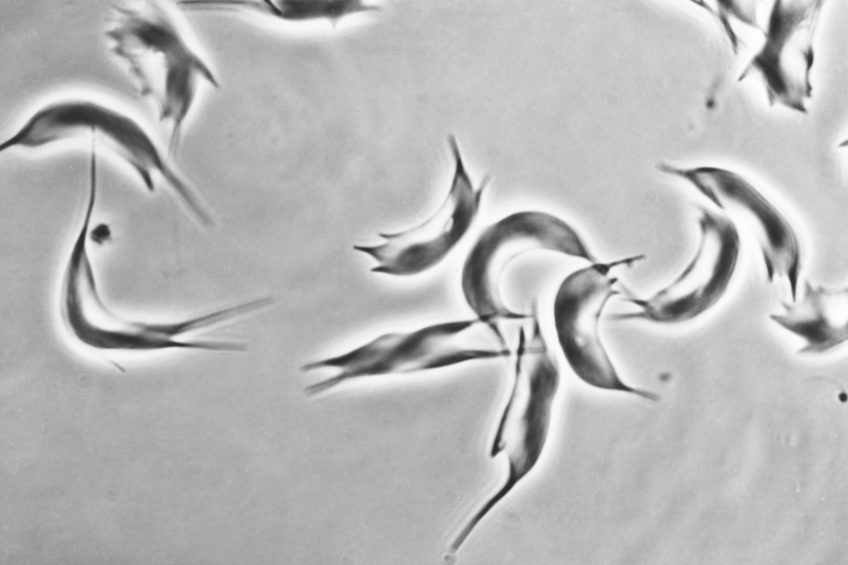

Globules rouges en forme de faucille (drépanocytose) ©Inserm/Chevance de Boisfleury, Anne-Marie